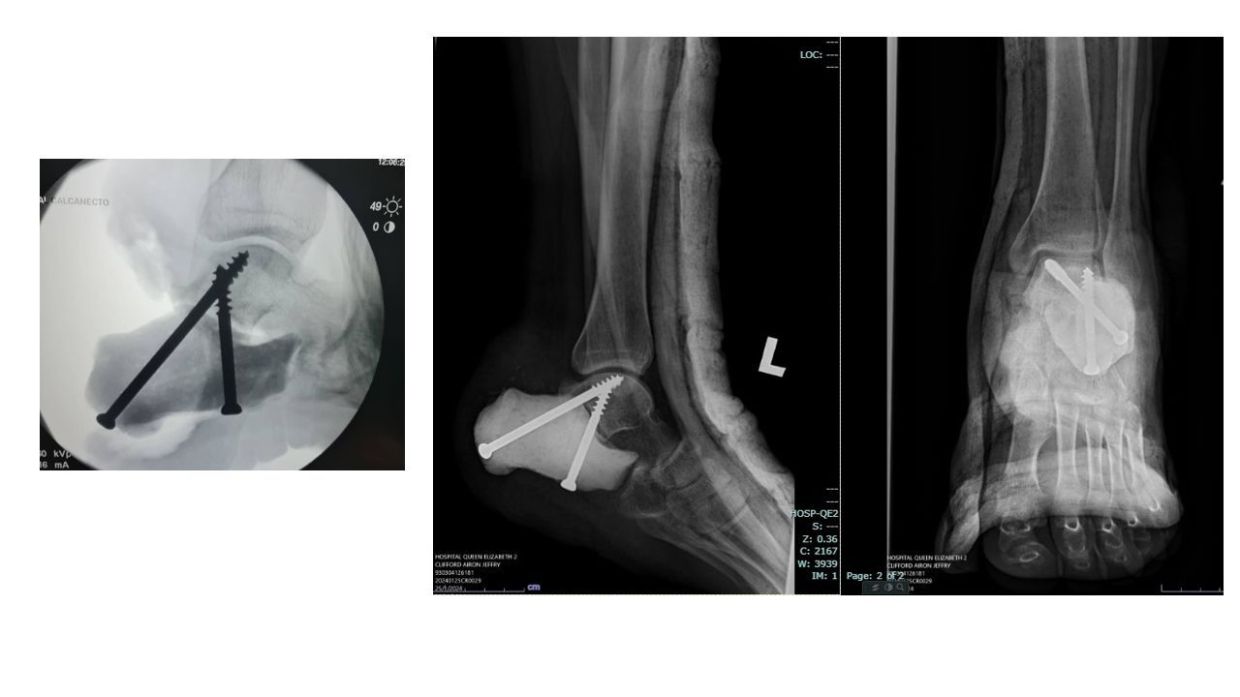

植入骨的 X 射线图像。(图片来源:伊丽莎白女王医院)